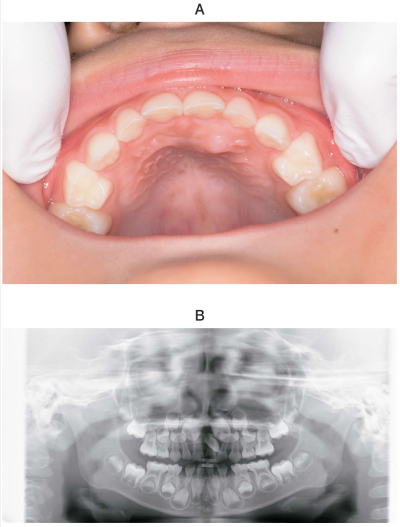

5歳の男児。口蓋の膨隆を主訴として来院した。1か月前に母親が気付いたがそのままにしていたところ、最近になって徐々に大きくなってきたという。初診時の口腔内写真とエックス線画像を別に示す。

考えられる原因はどれか。1つ選べ。

a. 過剰歯

b. 歯牙腫

c. エプーリス

d. 上顎左側中切歯の位置異常

e. 上顎左側乳中切歯の歯肉膿瘍